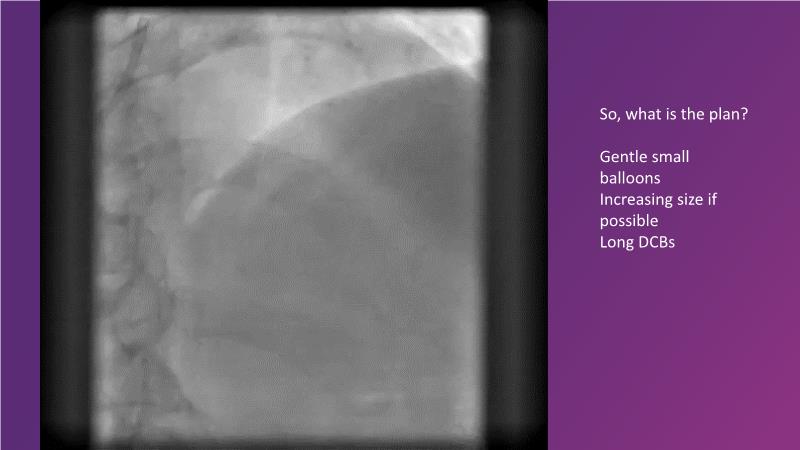

DES and DCB, can these two technologies be complementary for the treatment of the same patient? What are the advantages and how to proceed? You will know everything by watching this presentation based on concrete cases.

- To discuss cases when DCB and DES are complementary

- To review positive remodelling effect with paclitaxel DCB